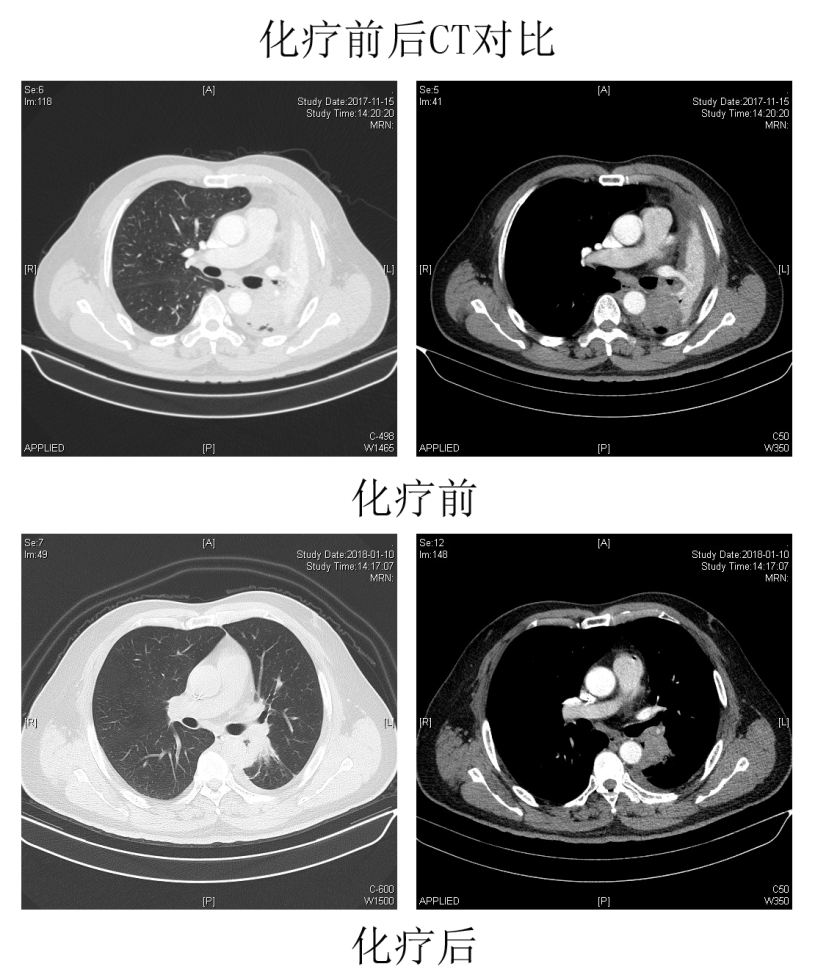

3个月前,家住福州的老王因“刺激性咳嗽、痰中带血”就诊我院呼吸内科,检查发现左肺中央型肺癌伴纵隔淋巴结转移、左下肺实变不张,肿瘤已到中晚期,完全阻塞了左主支气管末端,需要切除左侧全肺,才能根治肿瘤。

医院肺部肿瘤诊疗中心多学科(MDT)团队经过讨论,为老王制定了个体化治疗方案:术前新辅助化疗2周期后,由胸外科潘小杰主任医师团队实施单操作孔胸腔镜左全肺切除+系统性淋巴结清扫术。